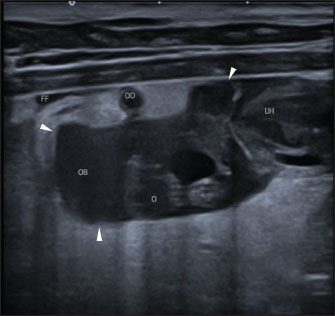

A Canon Aplio i600 ultrasound machine with convex (9-10.8 MHz) and linear (12-18 MHz) probes was used. The conscious patient was positioned in both the lateral and dorsal recumbencies. Moderate distension of both uterine horns (up to 17 mm in diameter) with immobile hyperechoic intraluminal content and irregular walls with multiple mural ovoid anechoic lesions were noted (Fig. 2). Cranial to the ovarian end of the right uterine horn and surrounding the right ovary, a 25-mm, well-defined, irregular lesion filled with mildly echogenic fluid was observed, which was compatible with a fluid-filled ovarian bursa. The adjacent peritoneum was moderately hyperechoic with a mild amount of free echogenic fluid (Fig. 3). A scant amount of free anechoic fluid was also present next to the uterine horns. A slightly tortuous tubular structure (up to 4 mm in diameter) with no color Doppler signal was identified running longitudinally adjacent to the ovary up to the uterine horn’s ovarian end, which was interpreted as the oviduct (Figs. 3 and 4). Moreover, both ovaries showed several rounded structures that were compatible with the corpora lutea. Vascularization near the lesion preserved the color Doppler signal.

Fig. 3. Abdominal ultrasonographic longitudinal examination in left lateral recumbency using a lineal high-frequency transducer in B-mode. Cranial is to the left of the image. The ovarian end of the right uterine horn (“UH”); the right ovary with nodular lesions (“O”), surrounded by a fluid-filled, well-defined lesion consistent with the right ovarian bursa (“OB”; the arrowheads mark the limits of the ovarian bursa). Surrounding this lesion, there is increased echogenicity of the peritoneal fat, as well as a mild volume of free fluid (“FF”). The thin, tortuous tubular structure, which is transversally imaged in this figure, is compatible with the oviduct (“OD”).

Several routes of ovarian bursal infection have been proposed in the literature: ascending (via the uterine horn and oviduct), hematogenous, lymphatic, and transmural (Van Israël et al., 2002; Park et al., 2013; Rubio et al., 2014; Eurell and Peacock, 2019). An ascending route of infection was most likely in our case. This was based on the isolation of E. coli, the bacterium most commonly associated with canine pyometra, and the presence of ipsilateral pyometra with cystic endometrial hyperplasia and chronic endometritis, which are frequently linked to this disease (Van Israël et al., 2002; Park et al., 2013; Rubio et al., 2014; Eurell and Peacock, 2019). In two previously reported cases, the ascending route was also considered the most likely route, given that the pyometra was unilateral and ipsilateral to the OBA. In one of these cases, E. coli was also isolated from the ovarian bursa (Van Israël et al., 2002; Eurell and Peacock, 2019).